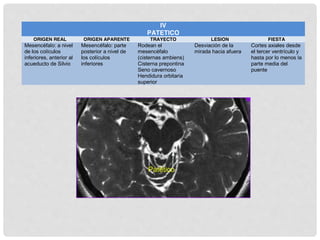

IV TROCLEAR

EL NÚCLEO SE LOCALIZA EN EL TEGMENTO DEL

MESENCÉFALO A NIVEL DEL COLÍCULO INFERIOR

CERCA DE LA LÍNEA MEDIA Y VENTRAL AL ACUEDUCTO

COMO EL NERVIO CRUZA AL LADO OPUESTO CADA

MUSCULO OBLICUO SUPERIOR ESTA INERVADO POR EL

NUCLEO TROCLEAR CONTRALATERAL

ENTRA POR

ENCIMA DEL

ANILLO

TENDINOSO

CRUZA LA LÍNEA MEDIA

ALCANZA EL

OS

CORRE EN DIAGONAL

JUNTO CON EP Y EL RS

AQUÍ SE

SEPARA

PARA

ENTRAR AL

JUSTO EN EL TERCIO

PROXIMAL

AXONES EMERGEN

ENTRE LA ACP Y LA

SUCA CON EL III NC

CORREN

ANTERIORMENTE

ENTRAN AL SENO

CAVERNOSO